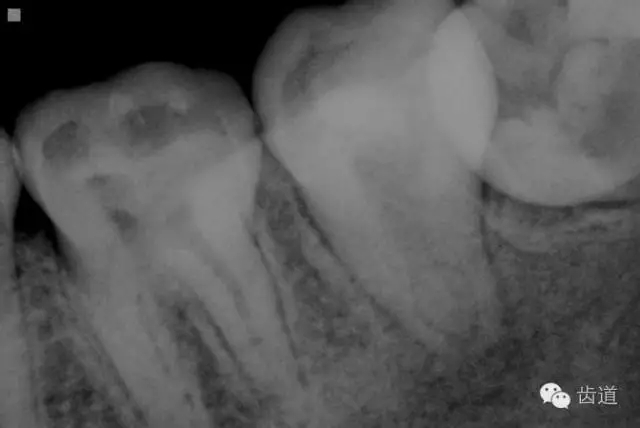

2. 術(shù)前X片

可見37根管影像清晰,根中上三分之二粗大,根尖三分一分為近遠(yuǎn)中兩根管,形態(tài)均呈弧形,根尖周膜連續(xù)性中斷,根尖周透射影明顯